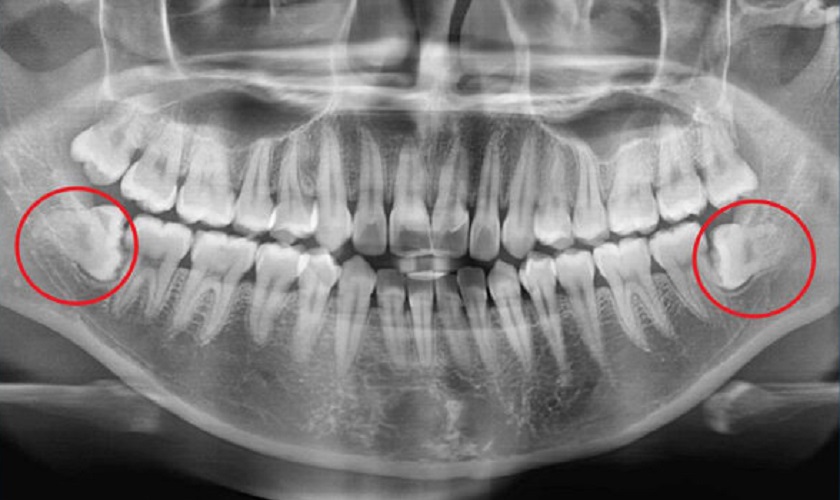

Để phòng tránh các biến chứng nguy hiểm thì biện pháp tốt nhất là loại bỏ răng khôn theo chỉ định từ bác sĩ nha khoa. Bạn sẽ cần chụp X – quang răng nhằm xác định hướng mọc, vị trí mọc răng. Dựa vào kết quả phim chụp, bác sĩ sẽ đưa ra kế hoạch và biện pháp nhổ phù hợp.

Phim chụp X – quang giúp bác sĩ chẩn đoán tình trạng và hướng mọc răng